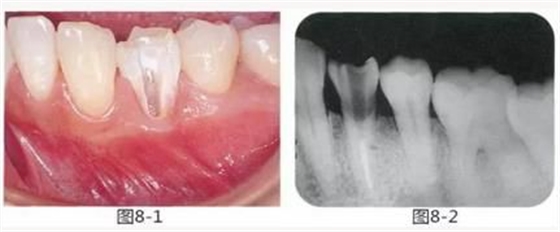

圖8-1 左下4頰側(cè)牙頸部有齦下齲壞,最終拔牙。齦下還殘留著感染的牙體組織。

圖8-2 左下4的X光照片。如果在此狀態(tài)下切除牙槽骨,就必須要犧牲鄰牙的支撐骨。